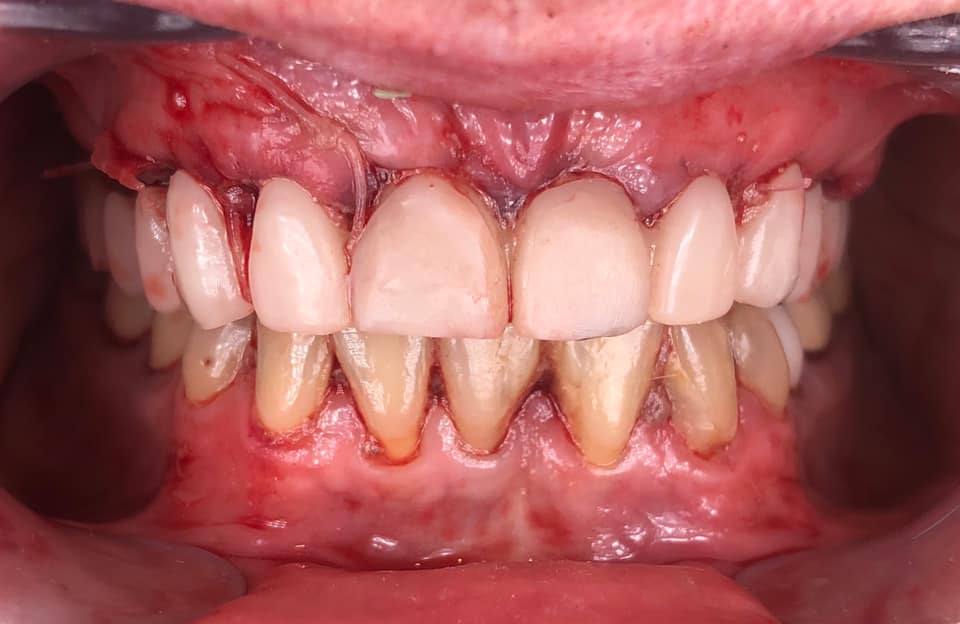

Below is a case of full arch same day temporization using the socket shield , root submergence and pontic shield techniques to preserve the site architecture . Neodent GM implants were placed in a guided fashion and same day temporization was performed using a milled PMMA.